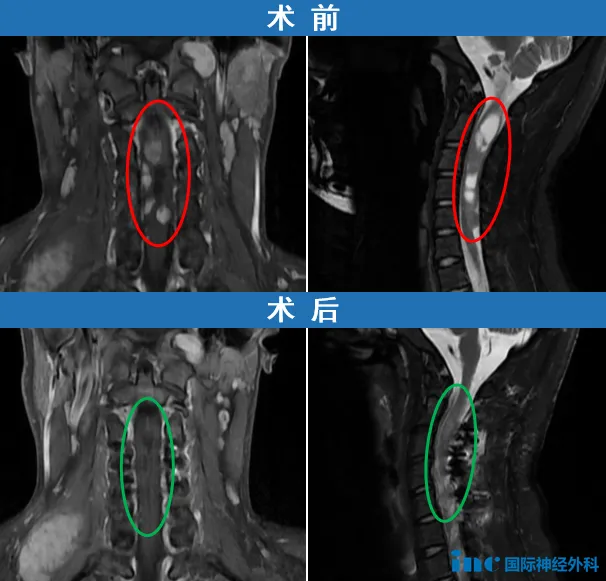

自2009年开始,18岁的帆帆便踏上了漫长的诊疗之路。4岁时接受首次神经鞘瘤切除手术,14岁确诊神经纤维瘤病2型,行右侧小脑病损切除术。2022年10月以来出现右下肢剧烈疼痛(持续可达6小时)及进行性听力下降。2025年7月复查显示后颅窝、颈椎椎管及胸壁多处病灶进展,右颈部病变达7.0cm×5.2cm。

巴教授评估认为三个部位的肿瘤需要外科干预:颈椎病变(因导致四肢麻木需优先处理)、后颅窝肿瘤(含听神经瘤和神经鞘瘤)及骶骨区域病变。治疗分三阶段进行:第一阶段处理颈椎病变(2025年10月23日在苏州大学附属第四医院成功实施高位颈髓占位病变切除术),第二阶段处理后颅窝肿瘤,第三阶段处理骶骨病变。